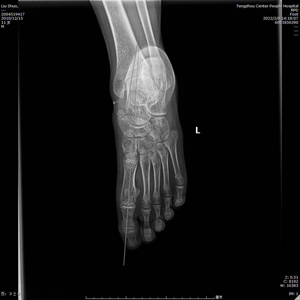

術(shù)中C型臂透視見:制動器位置良好,模擬左足負重試驗,患者足弓恢復(fù)良好。整個手術(shù)時間短,創(chuàng)傷小,見效快,僅用時30分鐘,微創(chuàng)刀口1cm,出血量不足5ml。術(shù)后左足石膏固定,2天后出院。?

(術(shù)后X線)